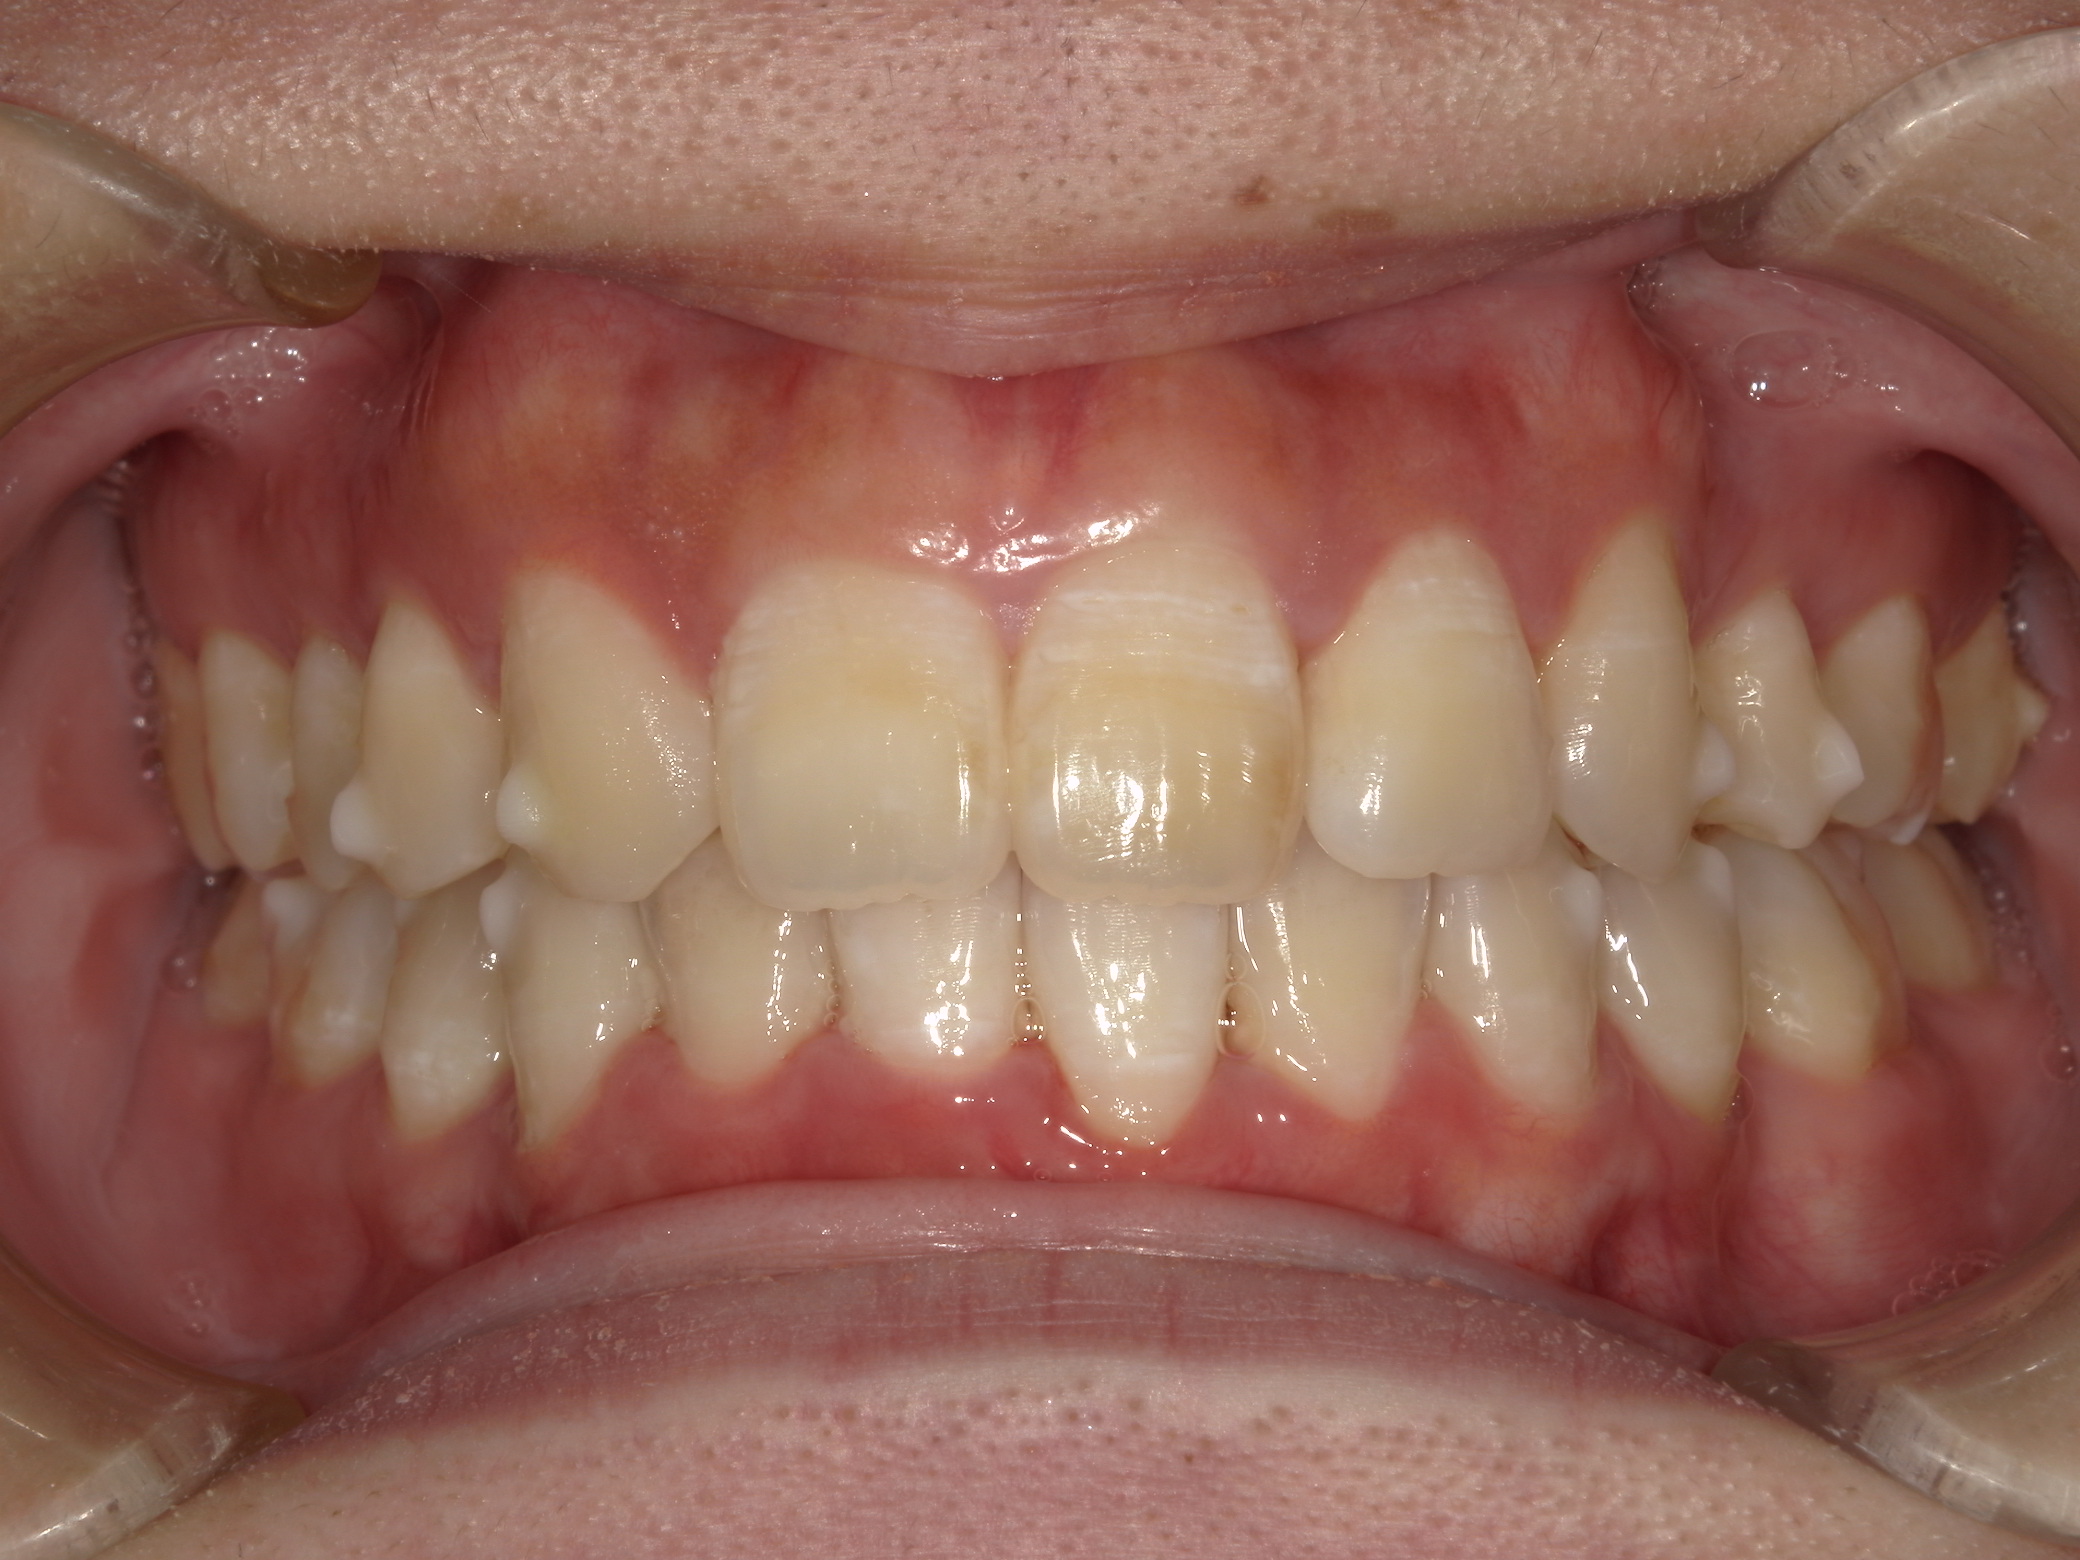

前歯の歯並びの乱れ(叢生)が気になる

| 年齢・性別 | 25歳女性 |

|---|---|

| 主訴 | 前歯の歯並びの乱れ(叢生)を気にされて来院された。咬み合わせや審美的な改善を希望されていました。 |

| 治療期間・回数 | 4年5ヶ月・30回 |

| 費用 | 1100,000円(税別) |